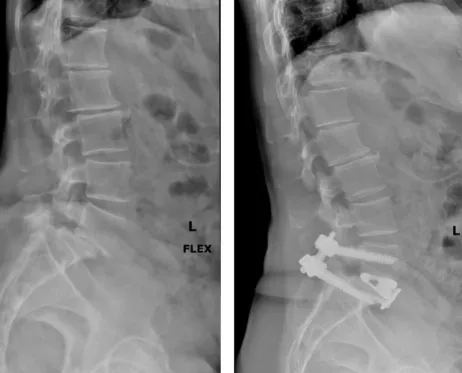

脊椎滑脫 手術有哪些?

椎間融合手術:在受損的椎體之間放置植入物,使它們更加穩定。

人工椎間盤置換手術:移除受損的椎間盤並替換為人工椎間盤。

椎間孔擴大手術:擴大椎間孔的大小來減輕椎間盤和神經根的壓力。

後路手術:在脊柱後方進行椎板切除、椎弓根切除等,減輕椎間盤和神經根的壓力。